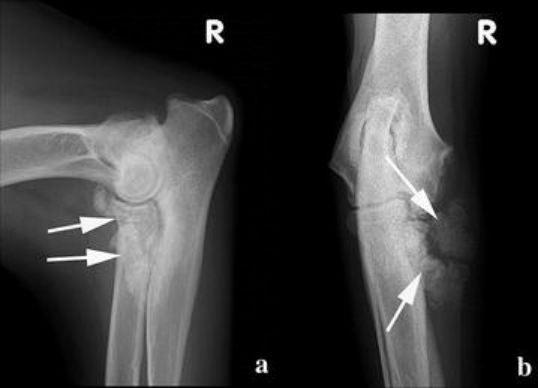

Fcp kan vara svårt att upptäcka röntgenologiskt. Hvorvidt der er tale om samme lidelse (fcp) hos hvalpe og voksne hunde,. Fcp services are also expected to reduce referrals into triage and secondary care physiotherapy services, enabling staff to move into first contact roles. Hältan är oftast värst efter vila och kan försvinna tillfälligt då hunden rört sig en stund. Die diagnose eines fcp ist häufig. Om hunden har problem med båda sidors armbågar kan. Like a unit trust in the uk, an fcp is set up in the form of a contract. Fragmented coronoid process (fcp) is a developmental defect of one of the coronoid processes, two small bony protrusions on the end of the ulna within the elbow joint. Röntgenförändringar kan vara subkondral skleros i trochlean, suddig/ojämn medial processus coroideus och inkongruens i leden.

Dadurch kann dieser knochenvorsprung frakturieren. Entry and exit system (ees) is provided by royal custom and excise department, ministry of finance and economy for the vehicle pass application from the owner and driver (allowed) to. Hältan är oftast värst efter vila och kan försvinna tillfälligt då hunden rört sig en stund. Röntgenförändringar kan vara subkondral skleros i trochlean, suddig/ojämn medial processus coroideus och inkongruens i leden. In seltenen fällen kann ein fcp auch durch ein trauma beim erwachsenen oder älteren hund auftreten. Die diagnose eines fcp ist häufig.

Röntgenförändringar kan vara subkondral skleros i trochlean, suddig/ojämn medial processus coroideus och inkongruens i leden. Entry and exit system (ees) is provided by royal custom and excise department, ministry of finance and economy for the vehicle pass application from the owner and driver (allowed) to. Derudover findes der faktorer, der kan øge forekomsten af ad hos de genetisk disponerede hunde.

Röntgenförändringar kan vara subkondral skleros i trochlean, suddig/ojämn medial processus coroideus och inkongruens i leden. Hvorvidt der er tale om samme lidelse (fcp) hos hvalpe og voksne hunde,. En af de vigtigste faktorer for fcp og uap er inkongruens.